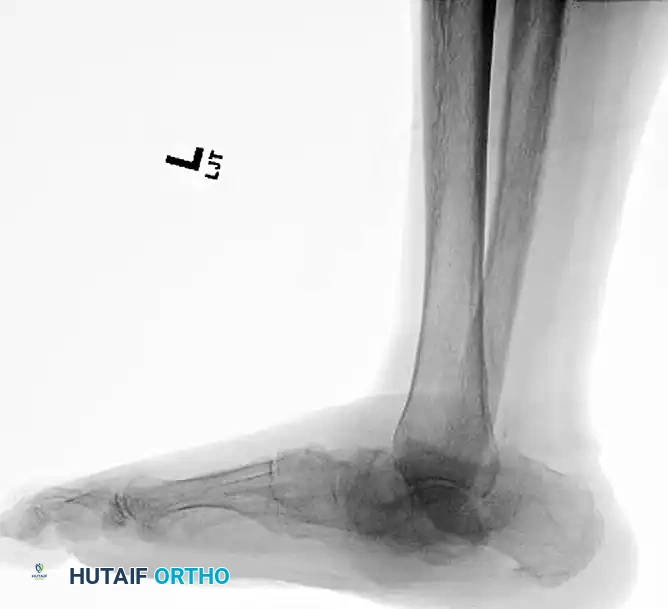

The following preoperative and postoperative radiographs demonstrate the successful application of augmented fixation in a young diabetic patient with a severe bimalleolar fracture-subluxation:

FIGURE 85-25 A and B: Preoperative radiographs of a highly unstable bimalleolar ankle fracture-subluxation in a 19-year-old man with a 12-year history of insulin-dependent diabetes mellitus.